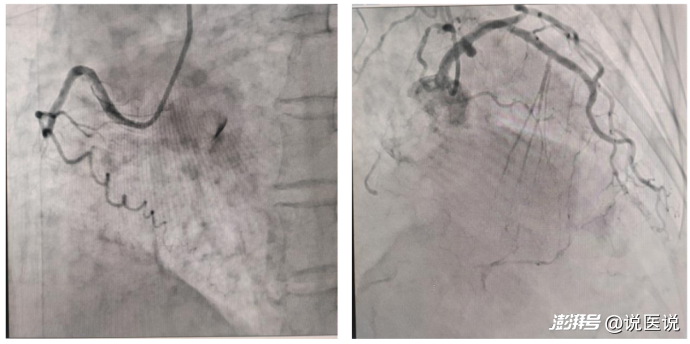

冠心病介入治療一科主任馮建欽為齊大爺進(jìn)行了全面細(xì)致的檢查與評(píng)估,結(jié)果不容樂(lè)觀——冠脈造影顯示其冠狀動(dòng)脈嚴(yán)重病變,LAD開(kāi)口段狹窄70%,近段狹窄40%;LCX近段狹窄80%,中段狹窄60%;RCA自中段完全閉塞,前向TIMI血流0級(jí),遠(yuǎn)端可見(jiàn)LAD、LCX逆向供血。其中RCA閉塞段長(zhǎng)達(dá)40-60mm,鈣化迂曲病變。

手術(shù)前影像